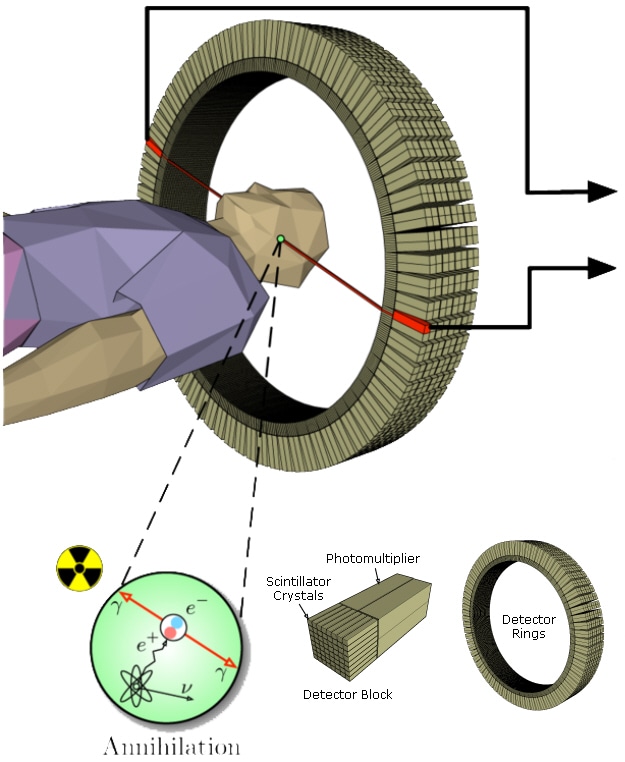

Figure 3: PET scan detector blocks and ring.

Positron emission tomography (PET) scans also involve ionizing radiation, only this time it is gamma rays that shine from the inside out from a radioactive tracer that accumulates in an area of interest. The material emits positrons that encounter nearby electrons, releasing a burst of gamma radiation. Two high-energy photons are released heading roughly in opposite directions from each other.

The trick is to identify these specific gamma inputs from other gamma noise. So for each gamma pulse you have to see whether a matching pulse occurred at the same time on the opposite side. This takes exact sensitivity and timing.

A circular detector contains scintillators that feed photomultiplier tubes (PMTs). Each PMT will typically be fed by more than one scintillator (see Figure 3). Because the PMTs will not be exactly matched, a variable-gain amplifier (VGA) is needed to tune the signal from each one. Each VGA requires a DAC to convert the digital control signal into the appropriate voltage. The signal can then be low-pass filtered before being digitized by a 10- to 12-bit ADC sampling around 50 to 100 Msps (see Figure 4). The entire chain must be highly accurate and low-noise, while keeping power under control and components small and compact. Analog Devices recommends their AD8332 VGA as one option for trimming the PMT signals before sending them through the filter to a AD9230 12-bit ADC, which can sample at up to 250 Msps.